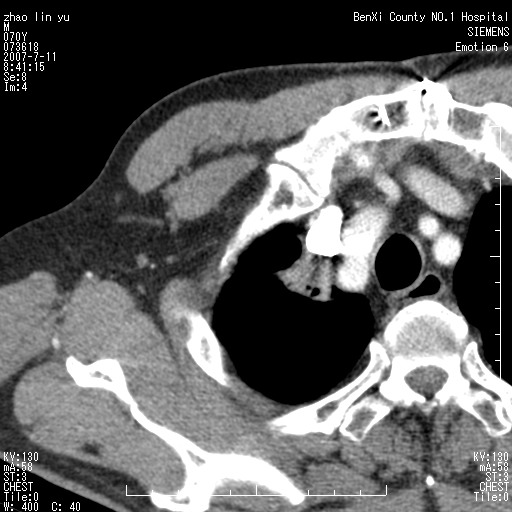

以下是引用王靖旗在2007-7-10 17:12:00的发言:[br] 男、70、咳嗽两个月,半年前换瓣手术,胸片未见异常,于昨天行x片发现右肺上野大片影,行ct扫描,这里是减薄图像,余肺正常。明天晚上会有增强扫描片,到时我会上传。[br][br] 冠状位请大家细看,应该是有意义的,[br][br] 请大家先看平扫发表意见。[br][br]